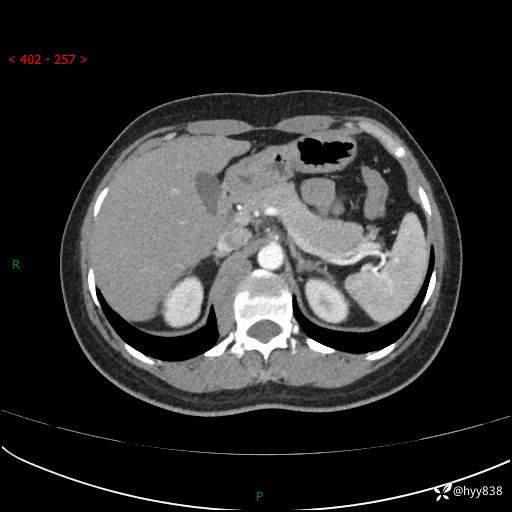

简要病史:患者于1天前因体检发现右旁肾占位,无肉眼血尿,无畏寒发热,无咳嗽咳痰,无腰腹部疼痛不适,无尿频尿急症状,起病来,患者未行特殊治疗,为求进一步诊治,门诊以"右侧腹膜后肿物"收治入院。 发病来患者精神、饮食、睡眠良好,小便如上,大便正常,体重无明显变化。

辅助检查:CT

临床诊断:腹膜后肿物

上腹部CT增强(动脉期+实质期)(外院平扫)